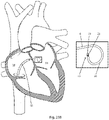

- medical device 20 include elongate member 6 comprising a distal curved portion 30 that has a distal end 28, such as the example of Fig. 7 .

- Distal curved portion 30 of Fig. 7 is shown in detail in Fig. 8 .

- Curved portion 30 is sufficiently flexible so that it may be substantially straightened out when it is inserted into a straight tube or vessel and may bend or curve when advanced through curved vasculature or other body lumens or when exiting the straight tube or vessel. Consequently, embodiments of medical device 20 having distal curved portion 30 may be used with a sheath and/or dilator for advancement through body lumens.

- An example of a curved portion 30 of medical device 20 is shown in Fig. 8.

- Fig. 8 illustrates one possible configuration of a curved portion: alternative embodiments of medical device 20 have a curved portion with a different shape or configuration, for example, the curved portion having a different size and/or radius of curvature.

- the particular embodiment of Fig. 18 in the illustrated position, includes a substantially 270 degree curve having a length dimension of about 10.5 mm ( ⁇ 50%), a lateral dimension of about 13.1 mm ( ⁇ 50%), the first 90 degrees of the curve having a radius of about 6.5 mm ( ⁇ 50%), and the last 90 degrees of the curve having a radius of about 4 mm ( ⁇ 50%).

- the curve is sized for fitting inside limited-size structures of human anatomy, for example, a left atrium.

- Embodiments of medical device 20 that have a distal curved portion 30 may be used for cutting through other types of tissue that are more readily accessible using curved devices such as a septum of the heart in a transseptal procedure.

- the distal end of medical device 20 emerges from a support catheter and punctures a septum, whereupon embodiments with a distal curved (or curled) portion (e.g. a 270 degree curve) facilitate performing the procedure by orientating the electrode towards the center of the curl and away from the opposite heart chamber wall after advancement through the tissue, in order to increase patient safety by reducing the risk of accidental perforation of a heart wall or other vital structure.